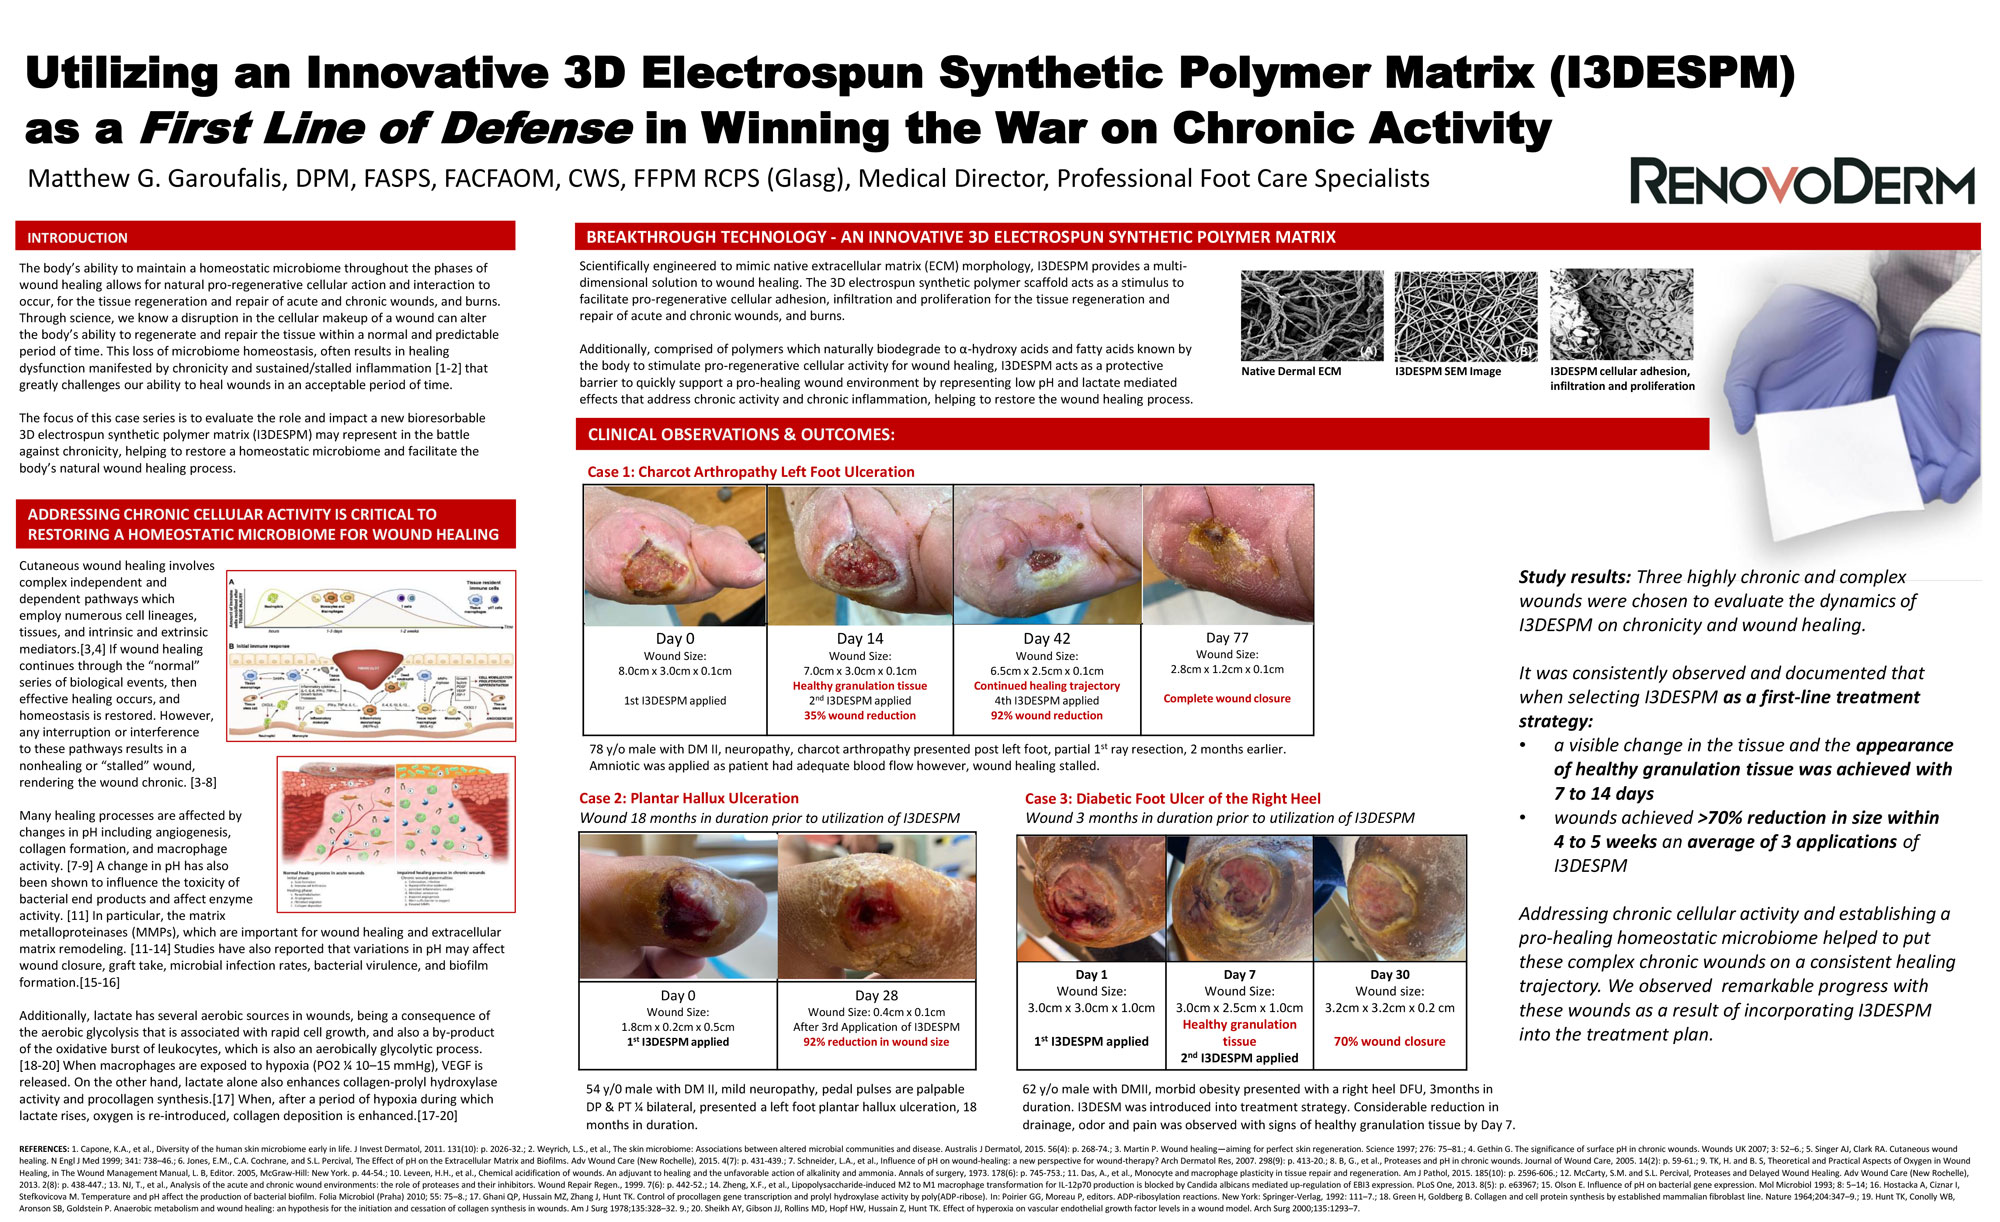

- The Phoenix Wound Matrix®, a fully resorbable, 3D electrospun device composed of synthetic polymers, is designed to provide a temporary microenvironment that supports endogenous wound healing, allowing for regeneration and remodeling of native tissue in the defect space/wound bed. This device is engineered to promote healthy tissue growth rather than a protracted inflammatory response.†

- For over a decade, Nanofiber Solutions, the technical parent company of RenovoDerm®, has worked with progressive surgeons and researchers to develop products designed to mimic the in vivo, microscopic, physical structures and properties of the extracellular matrix (ECM) vital to functional tissue regeneration.

- The Phoenix Wound Matrix®, a fully resorbable, 3D electrospun device composed of synthetic polymers, is designed to provide a temporary microenvironment that supports endogenous wound healing, allowing for regeneration and remodeling of native tissue in the defect space/wound bed. This device is engineered to promote healthy tissue growth rather than a protracted inflammatory response.†

- For over a decade, Nanofiber Solutions, the technical parent company of RenovoDerm®, has worked with progressive surgeons and researchers to develop products designed to mimic the in vivo, microscopic, physical structures and properties of the extracellular matrix (ECM) vital to functional tissue regeneration.